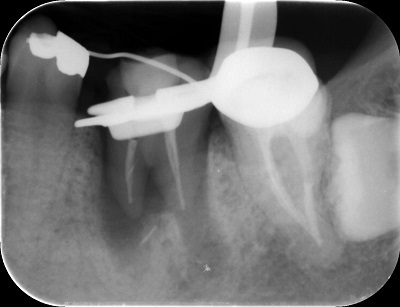

顕微鏡(マイクロスコープ)を用いて治療する

顕微鏡(マイクロスコープ )を用いて、中を観察することで、見落としがちな神経の管や、歯のヒビ、穴が開いている(パーフォレーション)、器具の破折片等をしっかりと見つけやすくなります。また顕微鏡用の器具と合わせて用いることで、余計に歯質を削りすぎないで、根尖まできちんと治療を行う事ができます。ラバーダムを行って唾液からの細菌感染等を防ぎ、顕微鏡を用いて微細な患部を観察し、根尖までしっかりと治療を行うことで、再発をさけることができます。

長期的な予後ではラバーダムを行ったイニシャルケース(初めて根管処置を行う場合)の成功率が約90%と言われています。